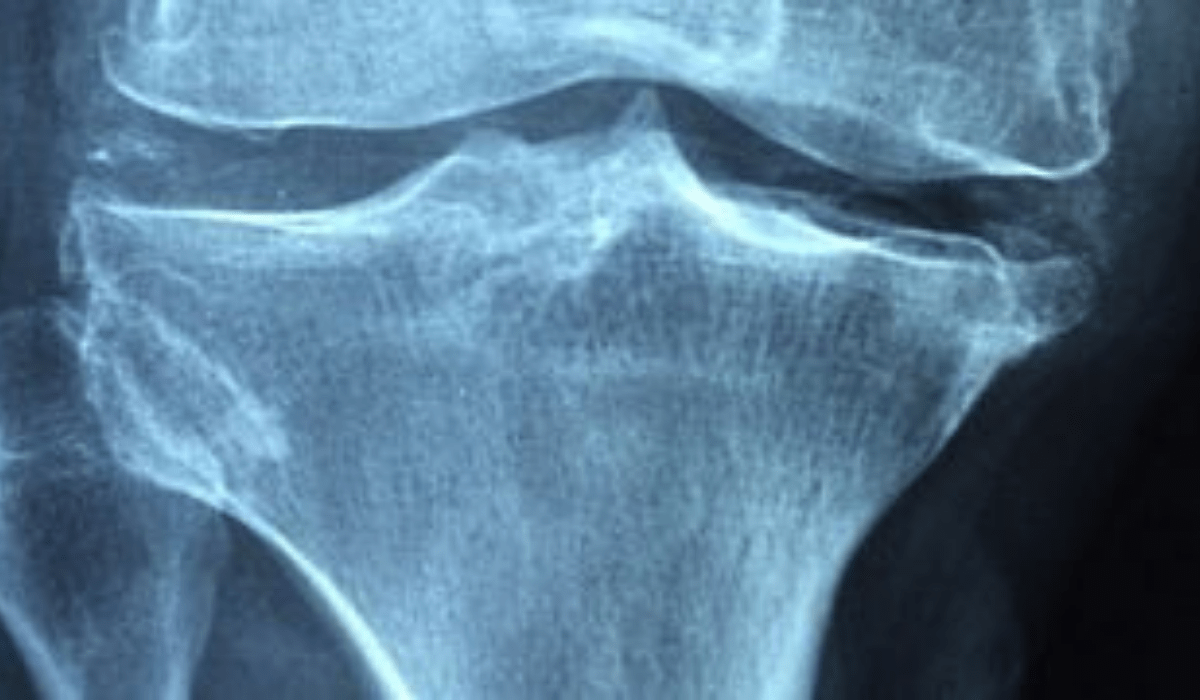

Um total de 531.431 pacientes com histórico de pedras nos rins foi identificado no banco de dados da VHA e 23.6% deles foram diagnosticados com osteoporose ou tinham algum osso quebrado na época em que o cálculo renal foi identificado. Os casos mais comuns eram de fraturas não relacionadas ao quadril, observada em 19% dos pacientes. Em seguida, vieram osteoporose (6.1%) e fratura de quadril (2.1%). A idade média dos pacientes que receberam diagnóstico ao mesmo tempo de pedra nos rins e osteoporose ou tiveram histórico de fraturas foi de 64,2 anos. A maioria dos participantes eram brancos e 91% deles eram do sexo masculino.

Entre 462.681 pacientes que não tinham histórico prévio de osteoporose ou fratura antes do diagnóstico de cálculos renais, apenas 9.1% haviam se submetido à triagem de densidade mineral óssea nos 5 anos após a identificação de pedras nos rins. Daqueles que completaram os testes, 20% foram diagnosticados com osteoporose futuramente, 2.4% com fratura de quadril e 19% com outros tipos de fraturas. Os pacientes com cálculos renais que foram submetidos ao exame de medição da densidade óssea e posteriormente diagnosticados com osteoporose eram majoritariamente formados por homens, representando 85% do total.

Segundo os pesquisadores, é provável que a origem dos cálculos renais não esteja relacionada à hipercalciúria, que é quando há alta excreção de cálcio na urina, mas à superabsorção do mineral pelo intestino em vez dos ossos. Os resultados do estudo sugerem, portanto, que a densitometria óssea seja realizada mesmo quando não há indícios de hipercalciúria.